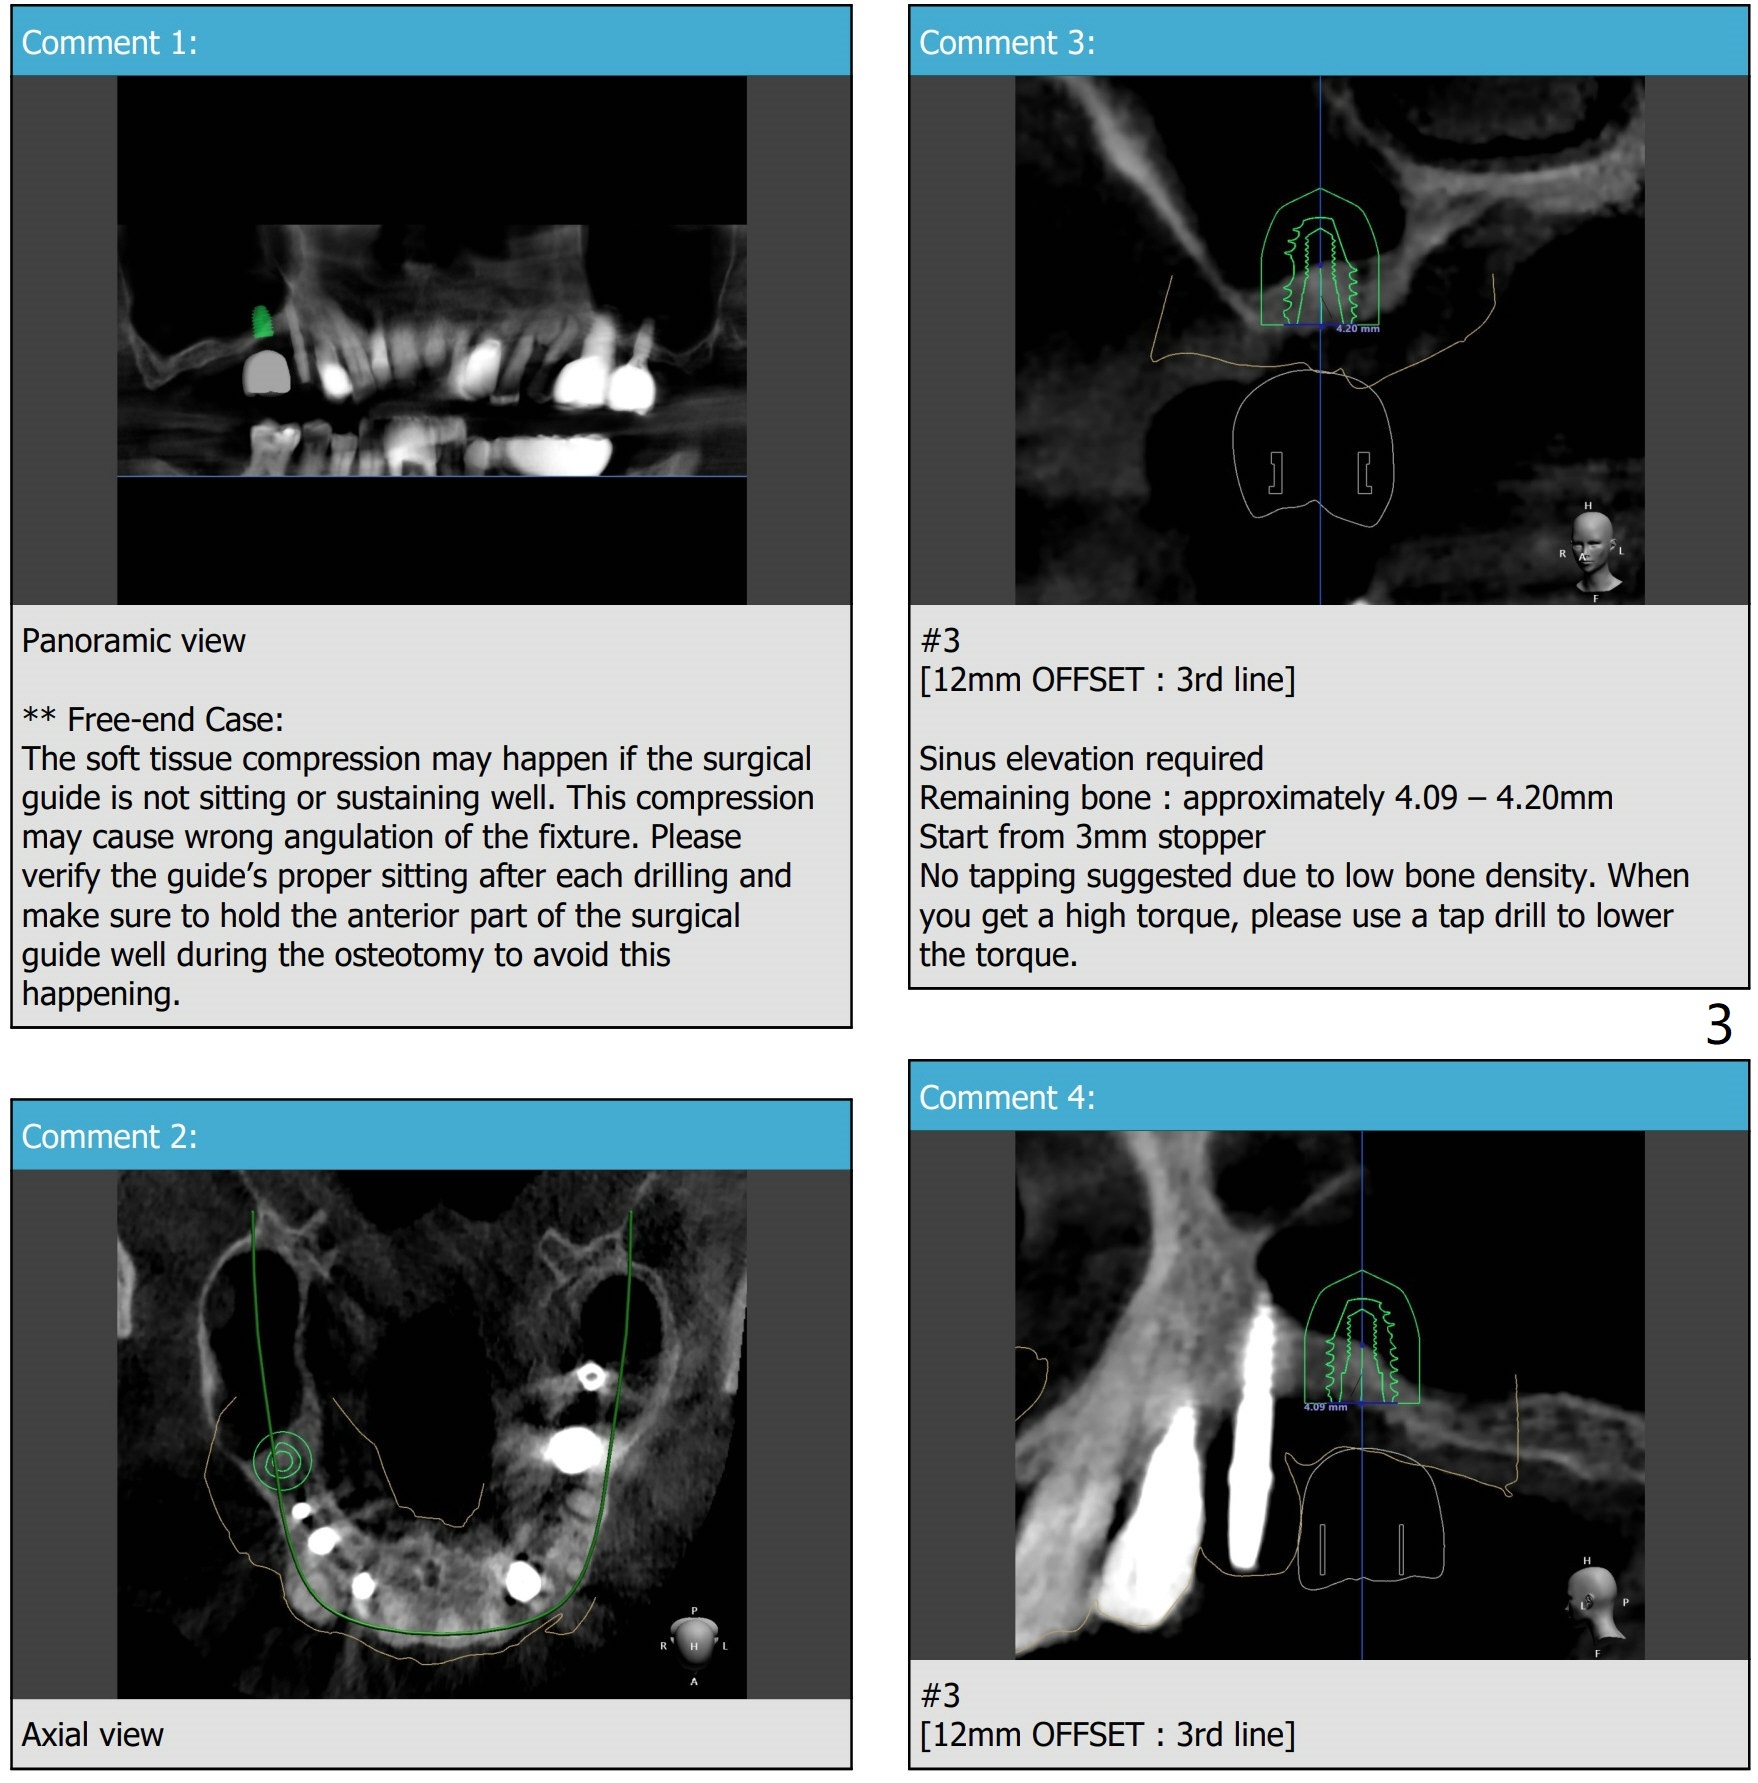

2nd Placement

Post implant removal and bone graft, the sinus floor must be soft and easily penetrated. Use Magic Sinus Lifter and sticky bone.